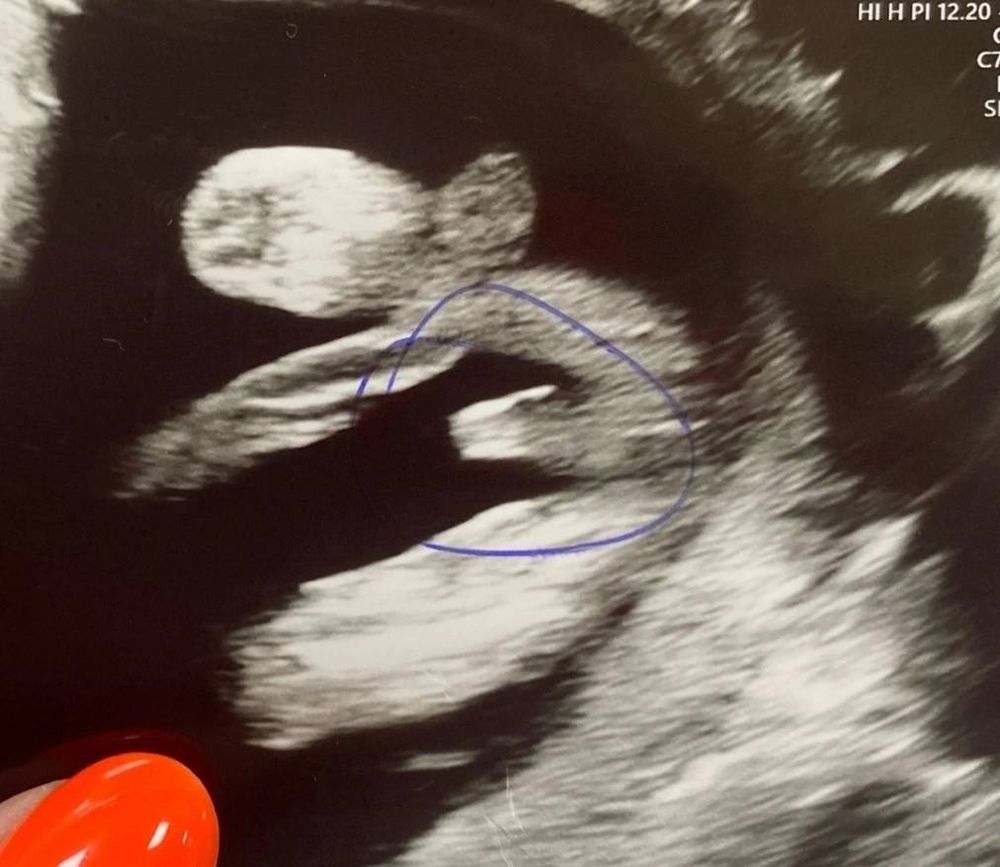

Добрый день! Как думаете, какого пола малыш?))

Пацан 100% , у нас с такого же ракурса было кофейное зернышко девчачее , у вас явно мальчуковое видно)

Вот не знаю, у моей на узи ( 13 недель) между ножками было чуть поменьше и уже, доктор определил девочку.😀 Хотя в предыдущую беременность было совсем пусто. Вам доктор пол предположил?

У меня точно такая же фотка,сказали мальчик Изображение на втором скрининге подтвердили